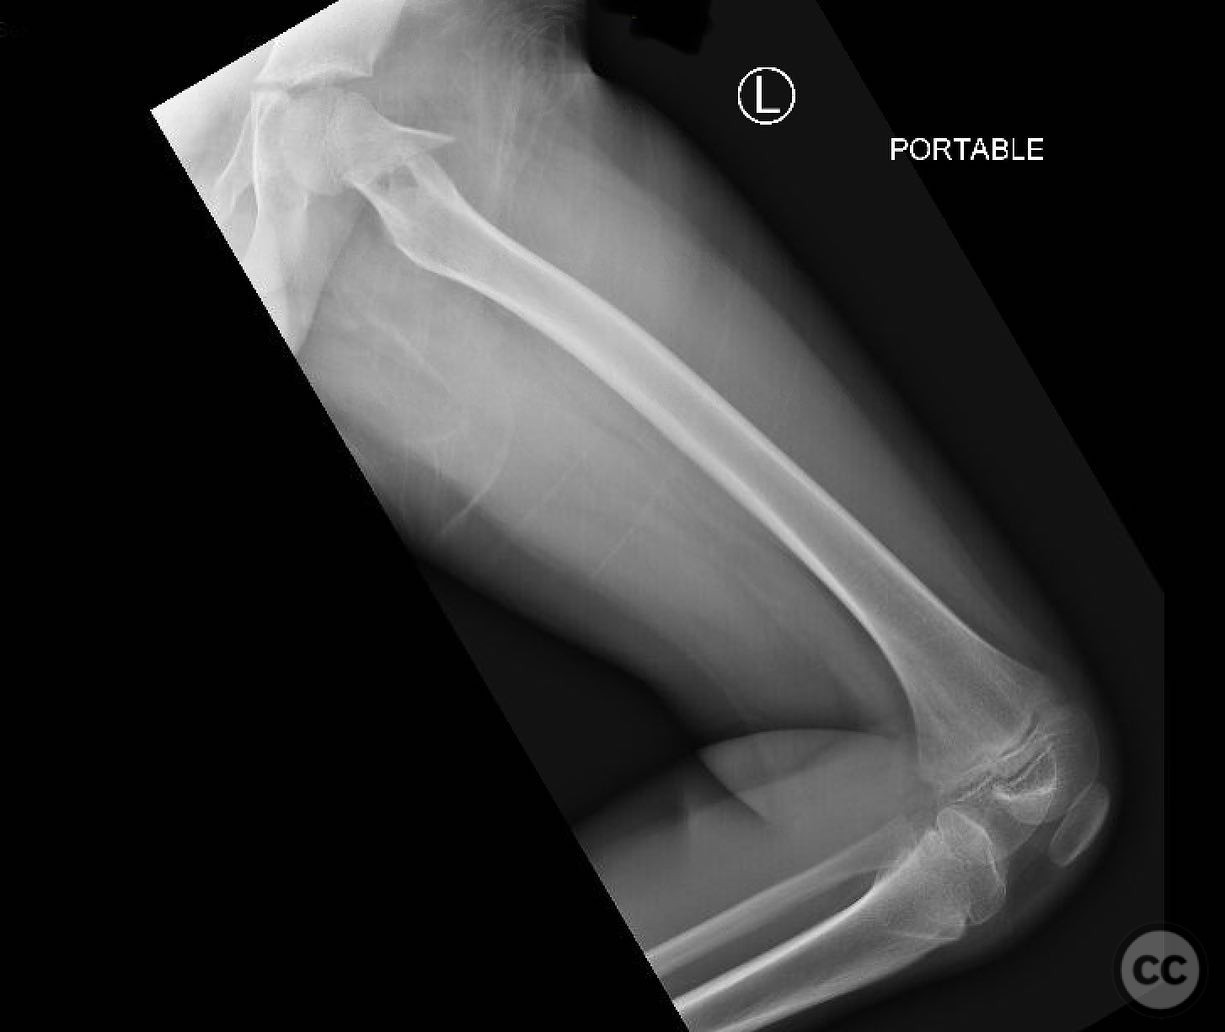

Femroal spiral fracture in a 4yo - TENS

Schleswig Holstein, Germany

Paediatric - PCCF